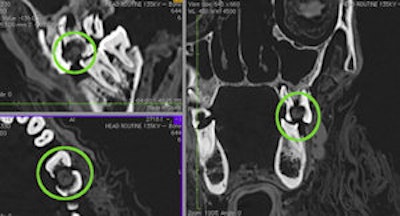

Multiplanar reformatted CT slices showing the packing material in the large interproximal carious lesion. Image courtesy of the International Journal of Paleopathology.','dvPres', 'clsTopBtn', 'true' );" >

| Multiplanar reformatted CT slices showing the packing material in the large interproximal carious lesion. Image courtesy of the International Journal of Paleopathology. |

The researchers also identified the mass previously found by Dr. Langsjoen in the carious lesions of the left first and second molars, and described it as a low-density, homogeneous ball of material, such as linen. It measures 7.7 x 7.1 x 3.7 mm, larger than the lesion's opening of 5.5 x 6.8 mm, but it remains loose within the cavity, they noted.

The mass is evidence of "therapeutic dental packing" that was used before death, according to the authors. No antemortem dental packing has been identified before, and this wasn't done postmortem, as the mass was not formed to the tooth's shape for a lifelike appearance and function in the afterlife, and not all of the cavities are filled, they explained. Also, the material wouldn't have been able to restore strength or stability to the tooth. But it may have delivered a medicine such as cedar oil or fig juice to treat the pain, prevented food particles from entering the cavity, and protected the nerve from contact with the tongue or foreign bodies, they noted.